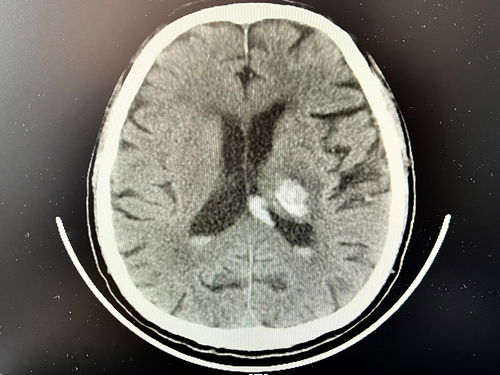

如果你的胸痛伴随着心悸、呼吸困难或面色异常等迹象,那就需要警惕心血管系统的问题。心肌炎、心包炎等罕见情况都需要通过专业的心电图、心脏超声等检查来进一步排查。